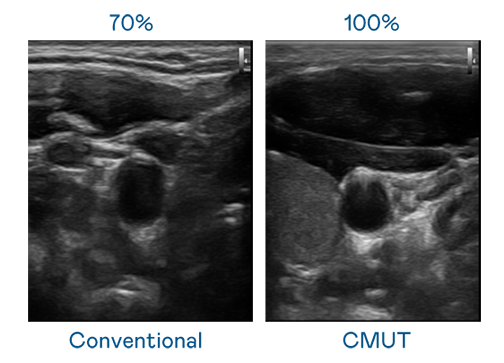

CMUT 技术是一种用电容式微机电元件来产生超音波讯号的技术。与传统 PZT 压电式技术相比,CMUT 频宽增加 30%,更宽频的超音波讯号让影像解析度大幅提升,是实现高影像品质医疗超音波扫描、促进精准医疗发展的关键技术。

超音波影像的解析度高低,首先取决于探头能发出的讯号频宽。银娱优越会 CMUT 可提供高清晰的超音波讯号,提供高频宽、高灵敏度、影像纹理细节更高的超音波影像,协助医护人员缩短影像判读时间及利用精准的医疗影像进行诊断。